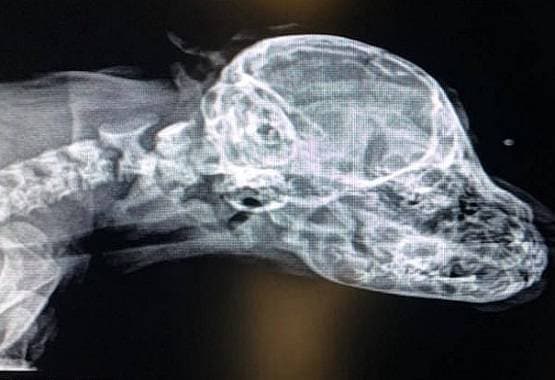

एक्स-रे बहुत ज्यादा एनर्जी वाली विद्युत चुम्बकीय विकिरण है। जिसे कई बार एक्स-रेडिएशन भी कह दिया जाता है। एक्स-रेज कई तरह के काम आती हैं। जिसमें टूटी हुई हड्डियों का पता लगाना, बीमारियों का पता लगाना शामिल है। इनका उपयोग सुरक्षा के लिए भी किया जाता है, क्योंकि इनसे छुपे हुए हथियारों का आसानी से पता लगाया जा सकता है।

वर्ष 1895 में एक्स रे की खोज करने वाले वैज्ञानिक विलहम रॉटजन थे, जो जर्मनी के रहने वाले थे। उनके नाम पर कई बार एक्स रेज को रॉटजन विकिरणें भी कह दिया जाता है। बताया जाता है कि पहला एक्स रे उनकी पत्नी का हाथ था, जिसमें उनकी शादी की अंगूठी भी शामिल थी। विलहम रॉटजन से एक्स रेज की खोज अनायास हुई थी।